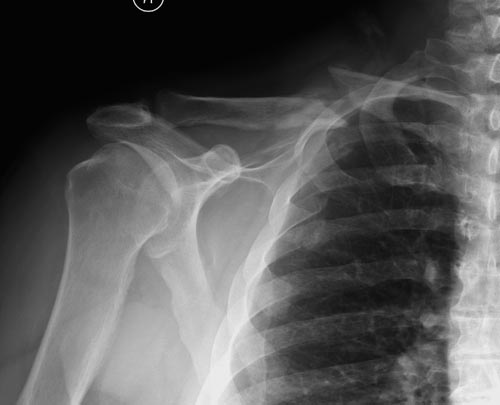

Болезненные ложные суставы надо оперировать, и здесь представлен случай

свежего болезненного ложного сустава, оперированного через 4 месяца.

Освобожден средний фрагмент и боковая компрессия лагированием, фиксация

пластиной..

Имя     : Clavicle 1.jpg

Тип     : image/jpeg

Размер  : 28591 байтов

Описание: отсутствует

Url     : http://weborto.net:8080/pipermail/ortho/attachments/20141124/0ee515fb/attachment-0033.jpg